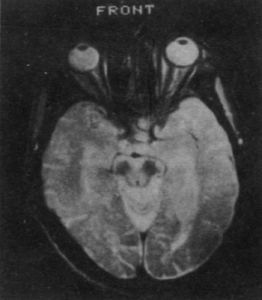

②血管性:多發性腦梗死病史、假性球麻痹、腱反射亢進、病理征和神經影響學檢查等可提供證據;

④血及腦脊液常規檢查無異常,CT、MRI檢查也無特徵性所見。